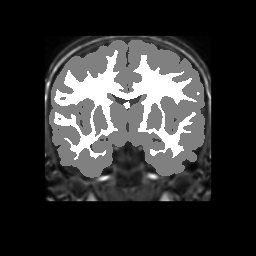

Accuracy is reported as Dice overlaps between a tool's segmentation and the Internet Brain Segmentation Repository (IBSR) manual segmentation for each of the 18 IBSR subjects. The inter-tool comparison (on the left below) shows the median Dice coefficient for each tissue class. The overlaps for FSL (from which the median values are drawn) are shown in the plot on the right.

Subject Accuracy (IBSR)

Overlap coefficients for each tissue class are shown here for each IBSR subject. Select a subject below to see the FSL results compared to other tools.